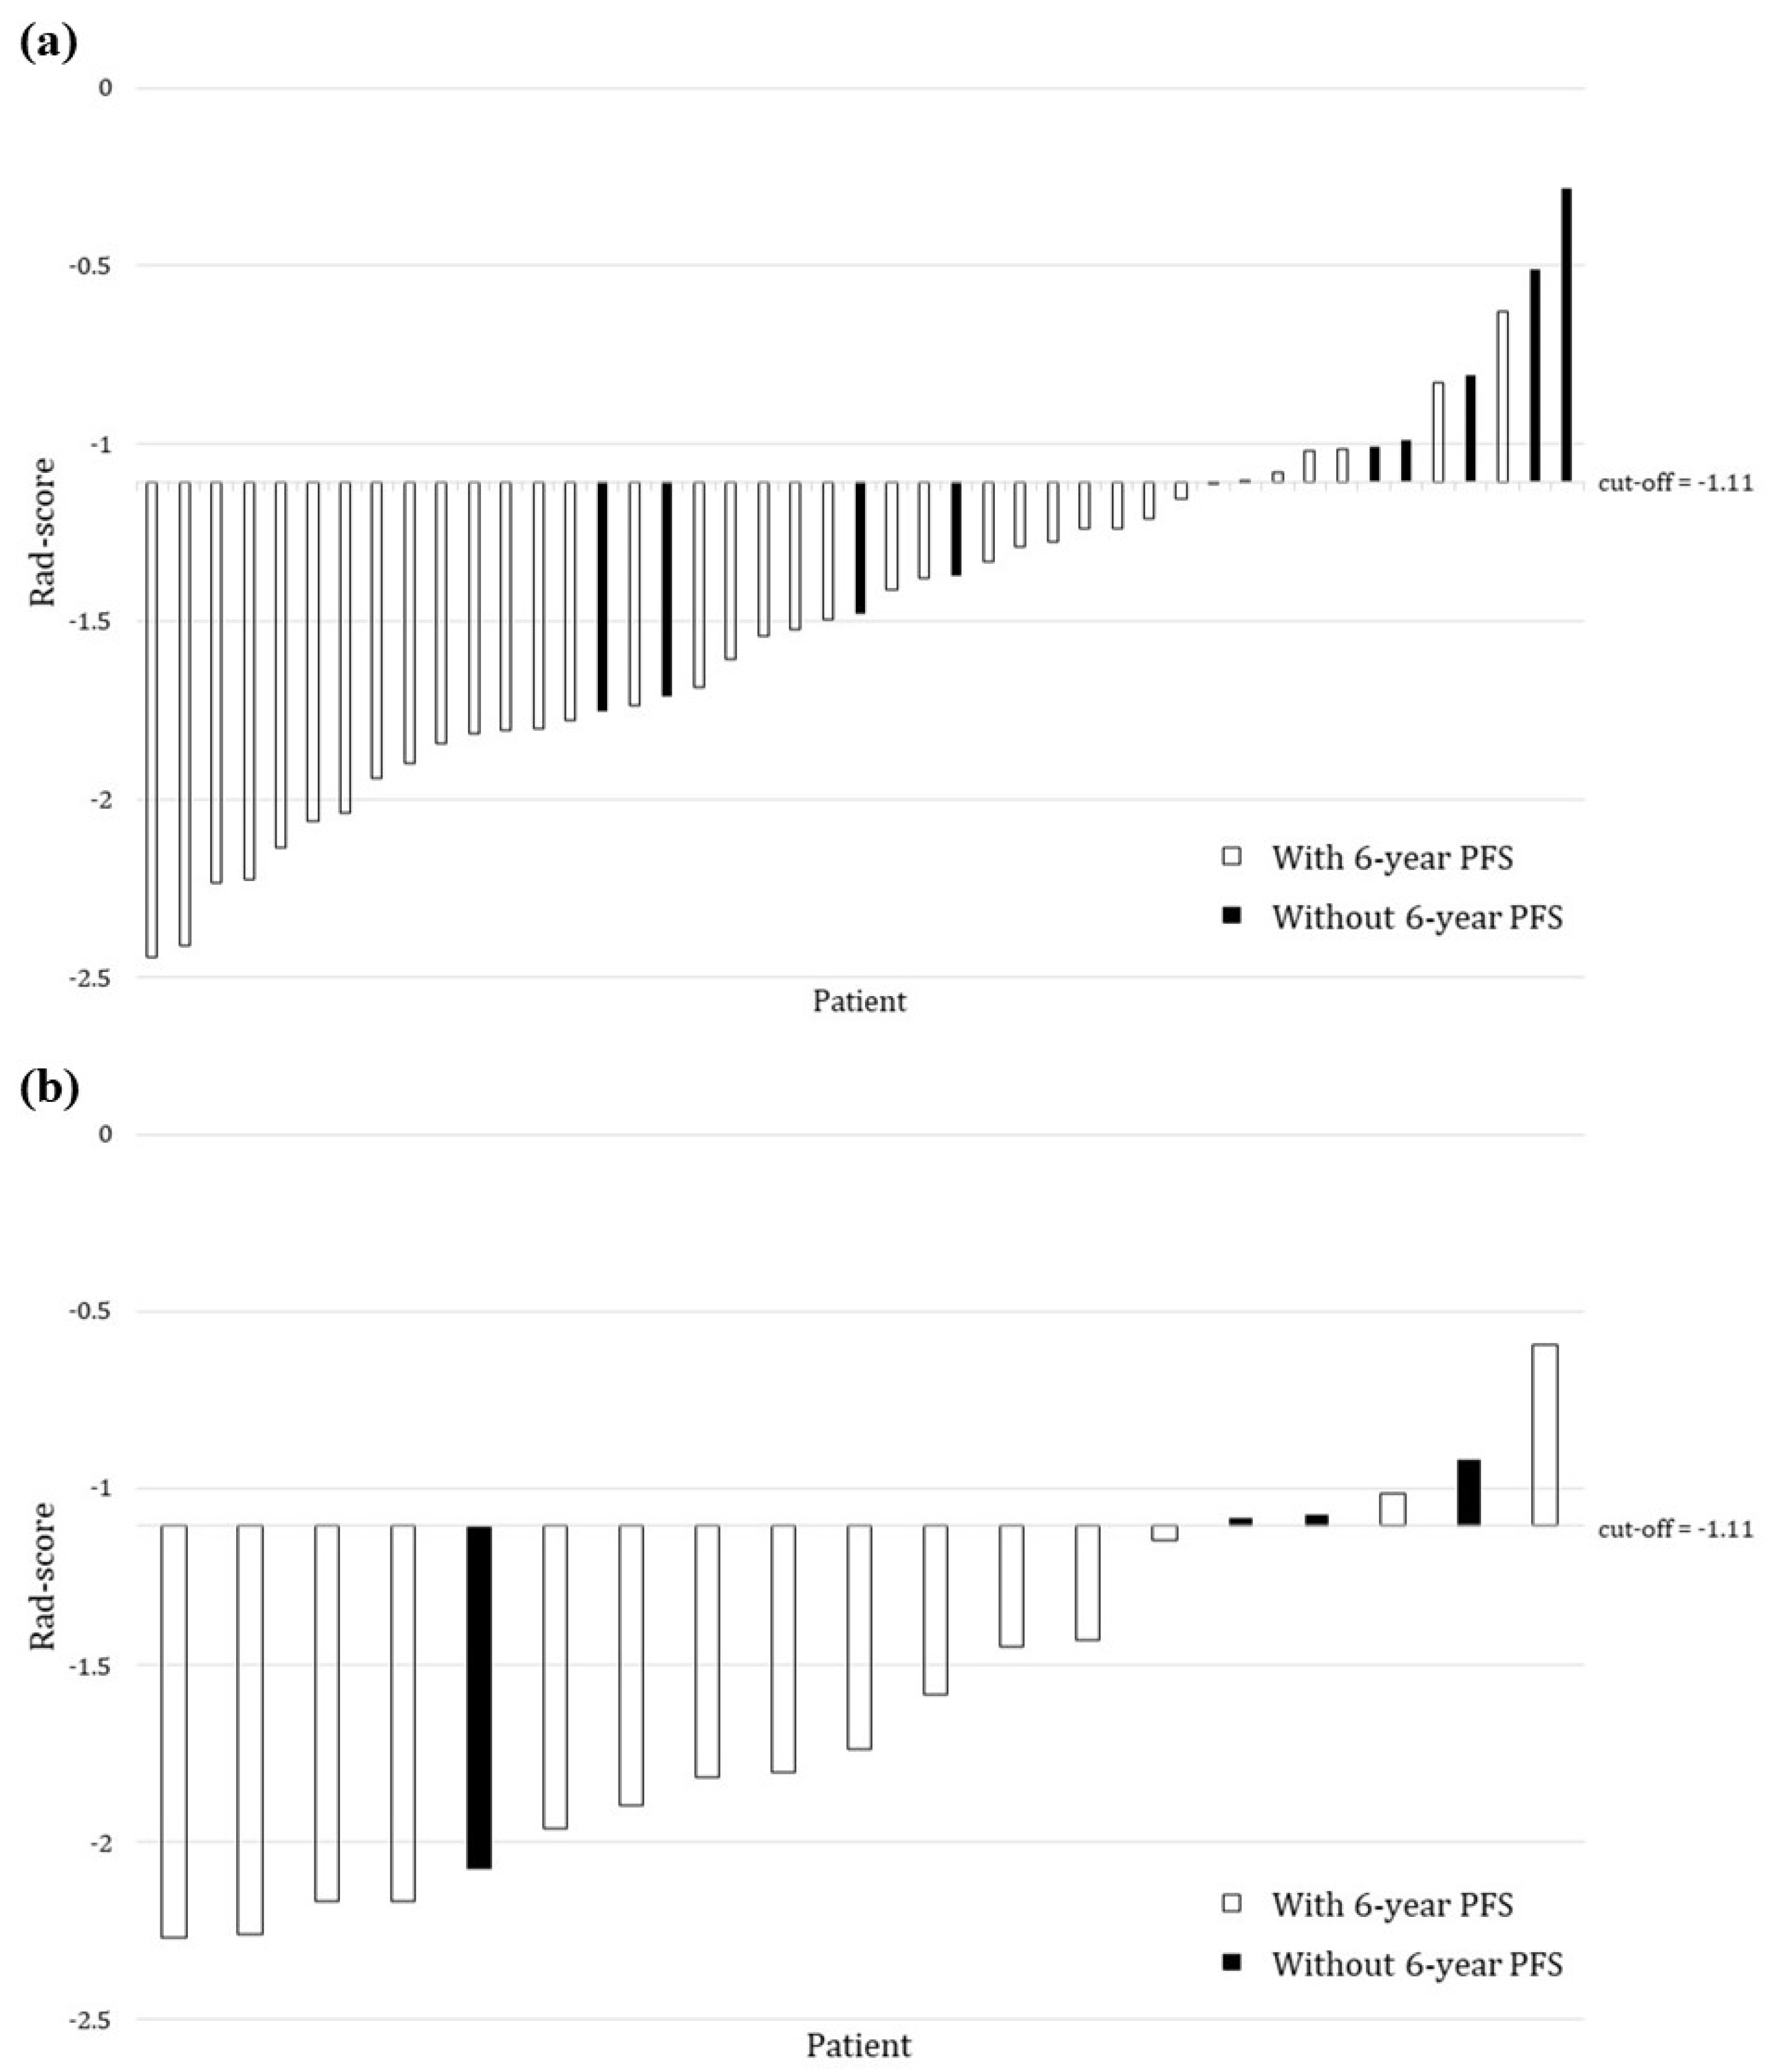

3. Results